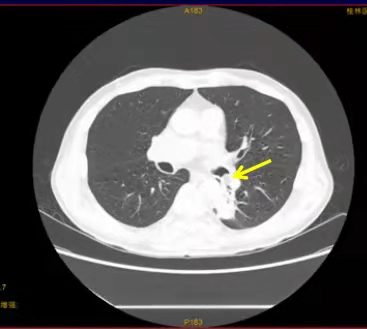

桂林医学院第二附属医院呼吸与危重症医学科拥有一支从事呼吸系统疾病临床和基础研究的高素质和稳定的人员队伍,医疗技术力量雄厚,为中国肺癌防治联盟桂北肺结节诊治联盟成员单位,广西呼吸专科联盟成员单位,桂北呼吸与危重症专科联盟核心成员单位,桂林市肺结节多学科诊治联盟牵头成员单位,“幸福呼吸”中国慢阻肺分级诊疗推广项目桂林地区牵头单位。科室医疗技术力量雄厚,业务精湛、服务优良,为患者提供优质医疗护理服务...